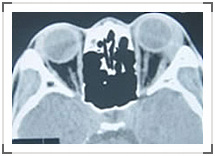

视网膜母细胞瘤是儿童眼内最常见的恶性肿瘤,有一定遗传倾向。单眼发病占60%-80%,其余双眼发病,少数还可伴有颅内松果体瘤或蝶鞍区原发性神经母细胞瘤。视网膜母细胞瘤早期由于患儿不能主诉而常常漏诊,累及后极部时,家长发现瞳孔区“猫眼样反光”。肿瘤可导致视网膜脱离和继发性青光眼,患儿因疼痛哭闹不止。肿瘤还可突破巩膜壁进入眶内,导致眼球突出,甚至经血道转移全身。B超显示眼底肿物突入玻璃体腔,以及视网膜脱离。CT显示眼内高密度肿块,常有钙化。视网膜母细胞瘤应尽早手术,局限于眼内者做眼球摘除,侵入眶内者做眶内容物摘除,术后放化疗。该瘤预后不好,易复发。